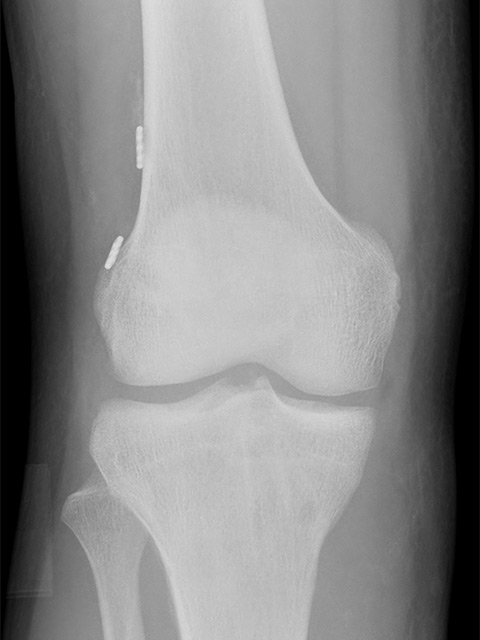

X光:

可排除骨折或有碎骨於關節內。